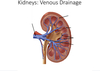

What is the arterial ‘supply’ of the kidneys

Renal arteries, which divied into five segmental arteries (4 anterior and 1 posterior)

These then divide to lobar arteries, then interlobar arteries, arcuate artereis and then interlobular arteries